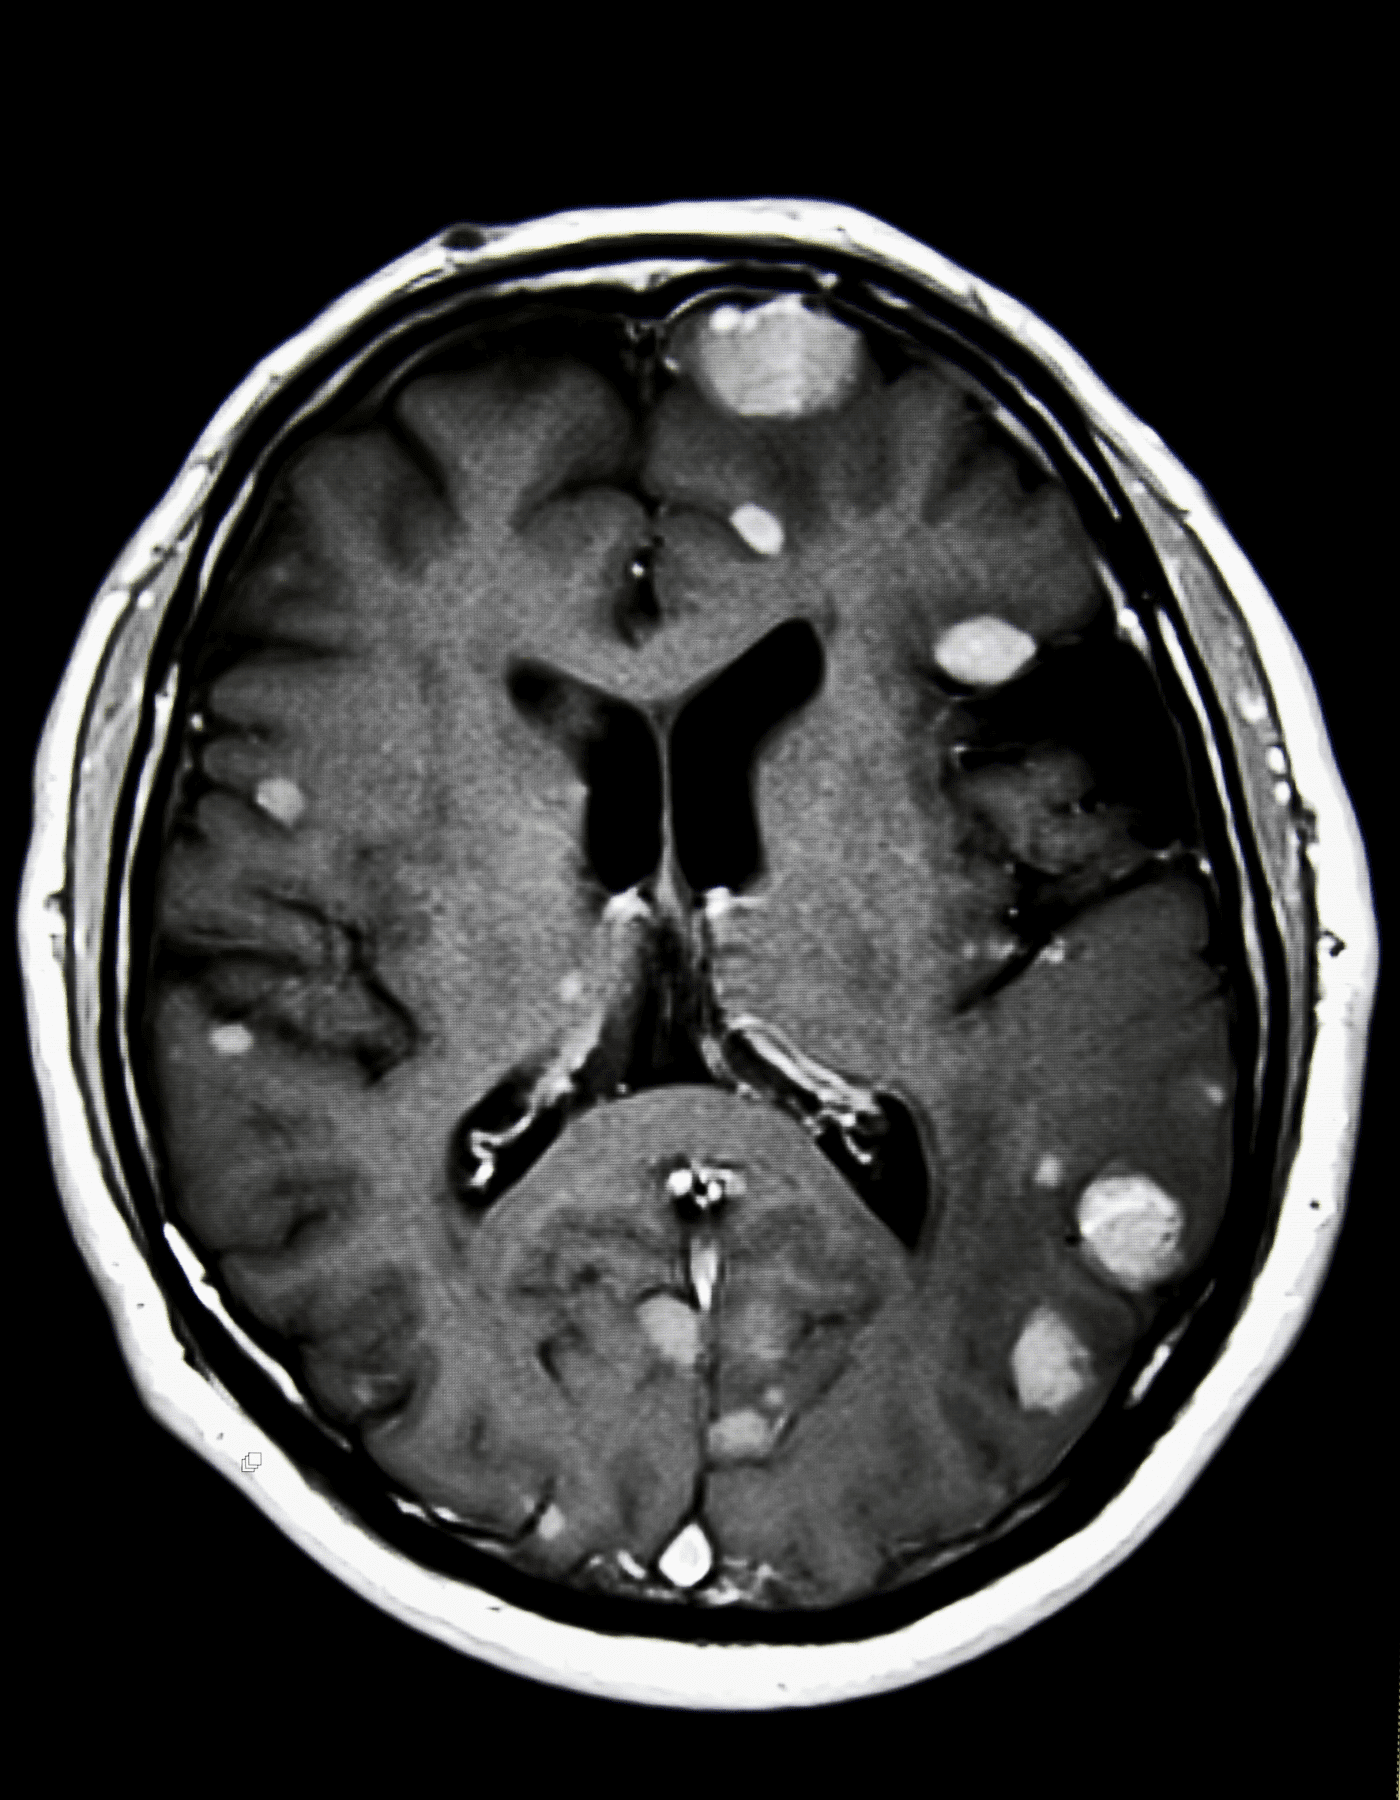

Craneotomía y Tumorectomía